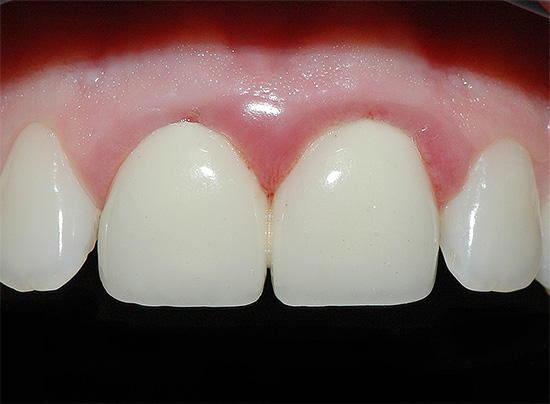

Con la posizione aperta della carie di cemento sui denti anteriori in combinazione con la carie cervicale, di norma, già allo stadio di un punto cariato senza una cavità cariata e nessun sintomo, si possono sospettare seri problemi e consultare un medico. Inoltre, in questo caso stiamo parlando della comodità di comunicare con i propri cari, amici, colleghi e altre persone. La comparsa di punti scuri, una sfumatura gessosa di smalto, le sue crepe e le schizzi al bordo con la gomma consentono di determinare la carie di cemento nella fase iniziale di sviluppo, quando può ancora "sfondare" nell'area subgengivale.